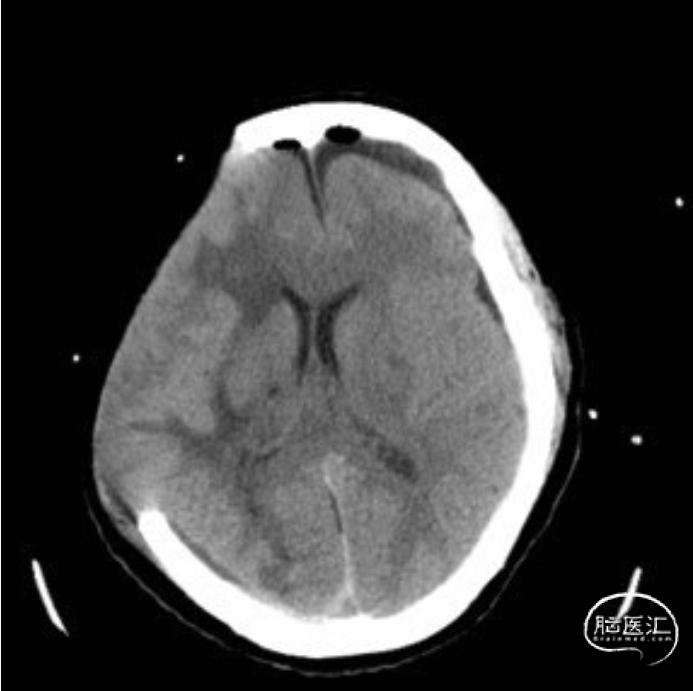

术后因为左侧硬膜下引流管欠通畅,患者逐渐出现意识障碍,复查头颅CT:左侧硬膜下积液增加,中线右偏。积极疏通引流管后患者意识障碍明显好转,复查头颅CT提示:硬膜下积液减少,中线回归明显。